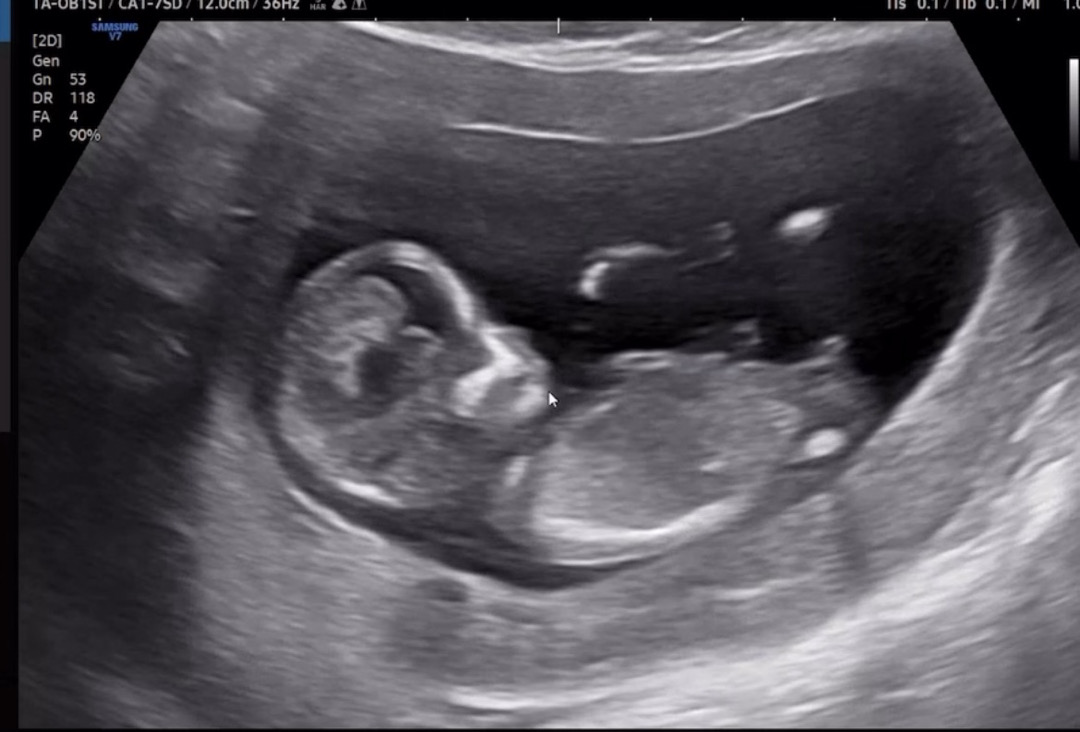

12주 초음파 사진인데 혹시 각도법 봐주실 수 있을까요 !!?? 순간 순간 캡쳐했는데 이 사진으로 알 수 있나요.. 고수님들 확인 부탁드립니다 🥹🥹📐🌶️🍑